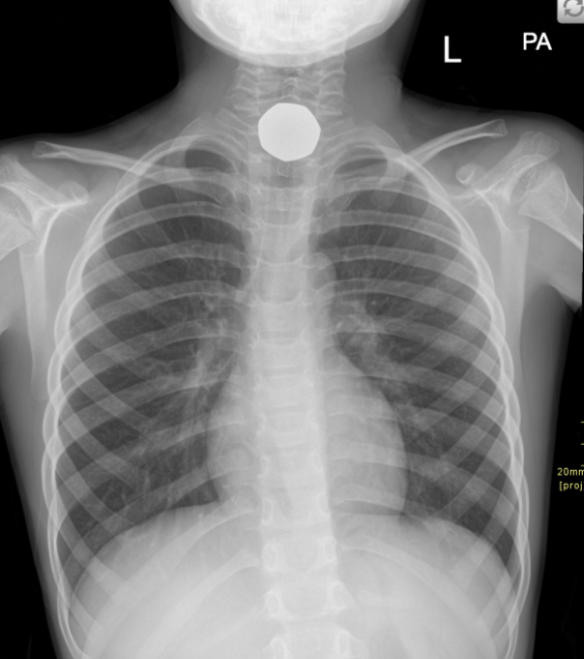

3. Swallowed 50p coin